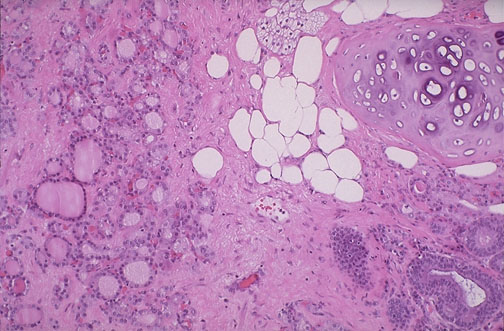

| Microscopically, this teratoma is seen to have cartilage, adipose tissue, and intestinal glands at the right, while at the left are a lot of thyroid follicles. The presence of abundant thyroid tissue within a mature teratoma can be termed struma ovarii. Rarely, a struma ovarii can even be a cause for hyperthyroidism. |